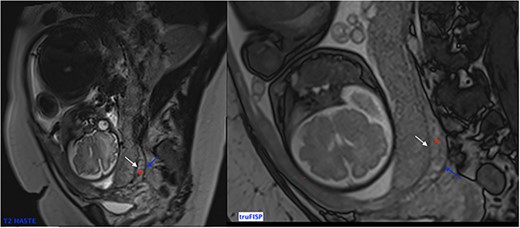

Diffusion weighted images can also be used to better see contours of the placenta [6]. It is important to note that MRI must be performed early enough to be able to plan childbirth and in order to decrease the false-positives (physiological placental changes at the end of pregnancy). Alamo et al. suggested performing it before 35 weeks of pregnancy while Lim et al. proposed before 30 weeks [7, 8]. Normal MRI signal of the placenta during at the end of 2nd trimester is a homogeneous isosignal aspect respecting the myometrium on T2-WI. As for the 3rd trimester, the placenta begins to have a more T2 hyposignal lobular and heterogeneous aspect. The myometrium usually has high signal on T2-WI (Fig. 4) with a trilaminar appearance.

Sagittal T2 Weighted Images showing normal MRI signal of the placenta and the myometrium at the end of 2nd trimester. Note the trilaminar aspect of the myometrium: retro placental layer in hyposignal (white arrow), intermediate layer (the zone of arcuate vessels in intermediate signal red asterisk) and the external layer (the serosa) with a thin T2 hyposignal aspect (blue arrow).